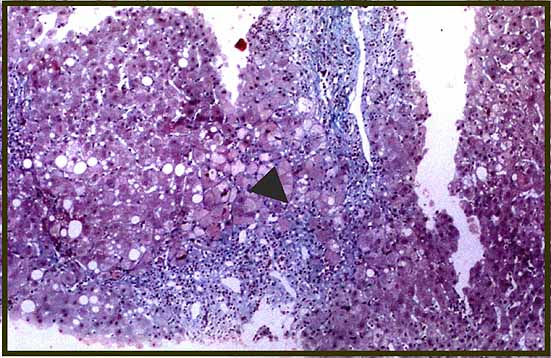

fig. 5

Figura 5.- Masson 100X; biopsia al 15º mes postrasplante con un puente fibroso porto-portal (flecha).